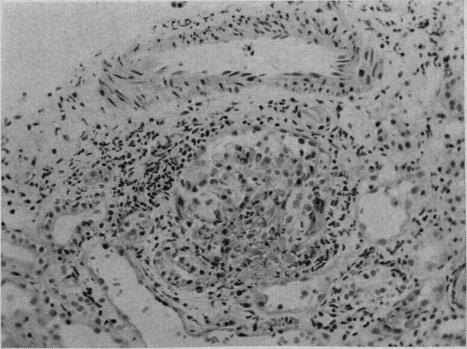

Three cases of Goodpasture's syndrome (pulmonary hemosiderosis and glomerulonephritis) are described. Each presented with unexplained hemoptysis and subsequently developed glomerulonephritis which caused uremia. These cases include the youngest and the oldest individuals yet reported with the condition. Steroid therapy was administered to one patient but apparently did not influence the course of the disease. The variations in the clinical course and the pathology of the disease are discussed.